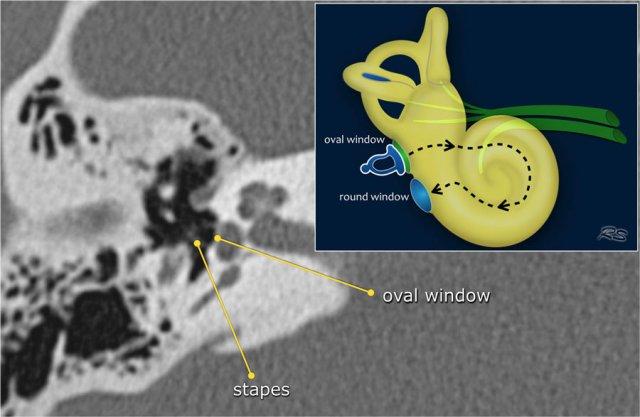

Cửa sổ bầu dục và cửa sổ tròn

Đế xương bàn đạp dao động ra vào so với màng tại cửa sổ bầu dục.

Các dao động được truyền từ cửa sổ bầu dục qua nội dịch đến các tế bào lông của cơ quan Corti trong ốc tai.

Cửa sổ tròn có chức năng giải phóng áp lực được tạo ra bởi các dao động dịch lỏng bên trong ốc tai, do đó đóng vai trò như một van giảm áp.